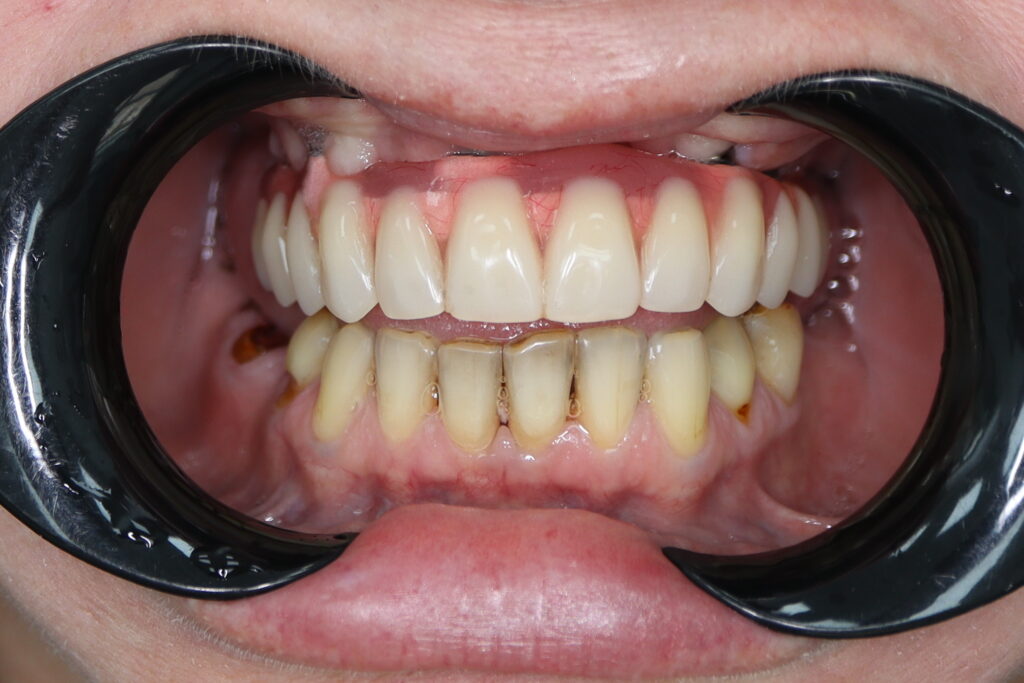

Результаты

Стоимость всего комплекса: 3500 USD (цена указана ориентировочно по курсу НБРБ на день оплаты)

результат тотальной имплантации